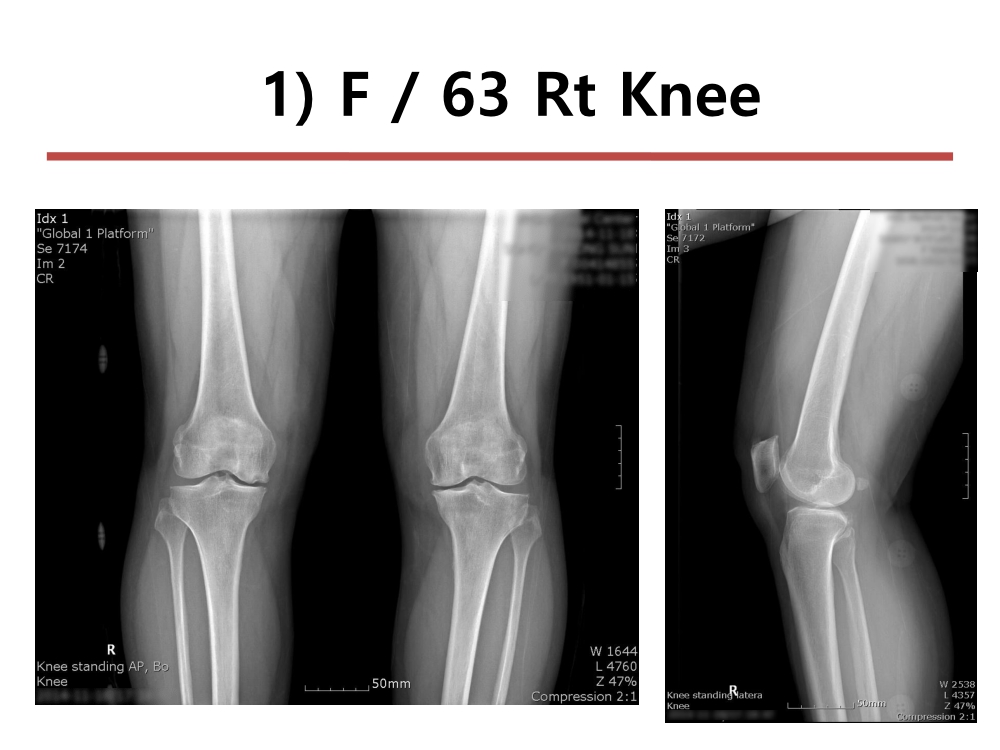

부천대성병원 윤정로 병원장님 슬관절 연수 강좌입니다.